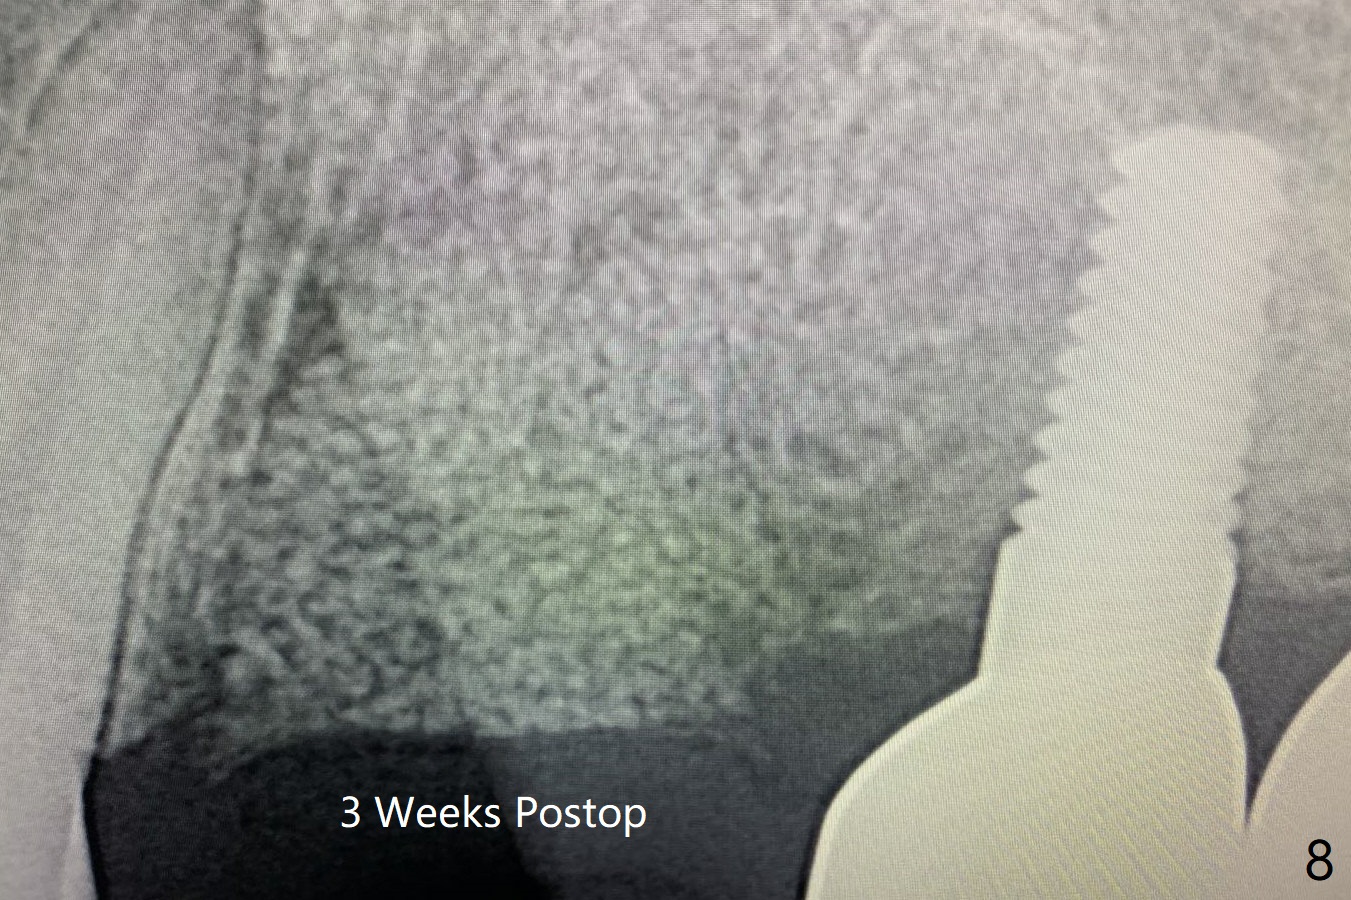

42岁女,12号牙断裂(图一),在拔除中不幸损伤13号牙,一起拔除,用GEM21S与异体骨和人工骨进行位点保存,术后骨粉一直脱落,病人觉得伤口有臭味。术后16天根尖片显示骨粉仍在牙槽窝(图二),伤口尚未愈合(图三),骨粉密度不高(图四,五)。讨论后,决定去除余留骨粉,重新刮拔牙槽窝,反复冲洗,最好放置粘性骨粉(图六),覆盖PRF和不可吸收膜,使用PTFE缝线,树脂敷料。术后三周膜和骨粉仍在原位(图七,八)。为了恢复龈乳头,术后四,五个月,利用导板去除两个牙位牙槽嵴骨质(图九),把植体植入牙槽嵴深部,之间便形成突起的牙槽嵴(图十:C)以及龈乳头。植牙整合后,利用临时牙冠,反复调整,挤压形成比较正常龈乳头。